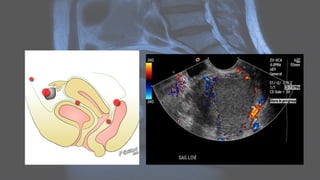

MRI

Ultrasound • Ultrasound isused to diagnose the presence and monitor the growth of fibroids: • uncomplicated leiomyomas are usually hypoechoic, but can be isoechoic, or even hyperechoic compared to normal myometrium • calcification is seen as echogenic foci with shadowing • cystic areas of necrosis or degeneration may be seen • Venetian blind artifact may be seen but edge shadowing +/- dense posterior shadowing from calcification is also typically seen 17

CT • fibroids areusually seen as soft tissue density lesions and may exhibit coarse peripheral or central calcification • they may distort the usually smooth uterine contour • enhancement pattern is variable